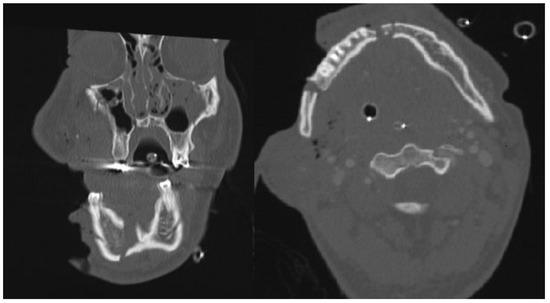

Computed tomography (CT) angiography images of the face, cranium, and the neck were obtained and revealed multiple fractures as follows: communitive fracture of the mandible; a Le Fort 2 fracture; a midline fracture of the maxilla; extensive fractures of the walls of the right maxillary sinus and both right and left orbital floor; a right zygomatic arch fracture; and fracture of the right temporal bone at the temporoman-dibular joint (Figure 2). Also noted were small hyperdense, spherical bodies, which correspond with remnants of explosive powder. Angiography revealed an arterial bleeding on the right side of the face. No intracranial or cervical injuries were found.

Figure 2. Preoperative computed tomography scan of patient 1, coronal and transversal plane, respectively.